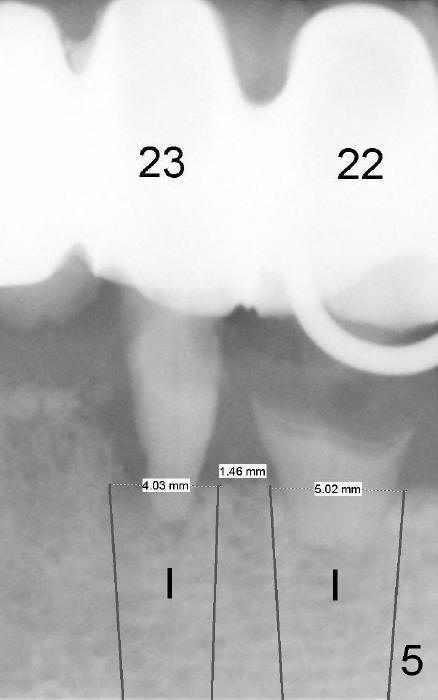

Since there is limited space between the lower lateral incisor and the canine, implants to be placed should not be too big. For example, if the diameters of the implants at the sites of #22 and 23 are 5 and 4 mm, respectively, there is less than 2 mm of bone between the implants (Fig.5). It is not safe. The bone may die.

It is safer if the diameters are reduced to 4.5 and 3.5 mm, respectively (Fig.4), as recommended by Dr. Borgner as follows. In fact, the implants for the lateral incisors are one piece, whereas those for the canines are two pieces.

Dr Wei, Because you have excellent vertical bone , I would conserve the interproximal bone by placing a 4.5 implant in both the cuspids and a 3.5 implant into the lateral region. Dr B